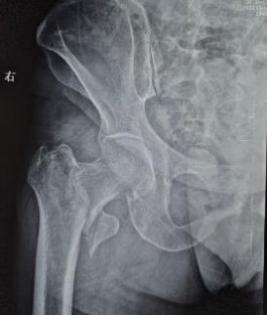

骨折X线片及CT

2022年6月,68岁的谈大妈不慎摔伤,导致右侧股骨粗隆间骨折,在当地一家医院接受了内固定手术。然而术后她的康复之路并不顺利——右髋持续疼痛,卧床三个月后尝试下地,发现每走一步都如同踩在针尖。就这样持续一年后,她因剧痛彻底无法行走,生活完全不能自理,整个人的状态瞬间跌入谷底。